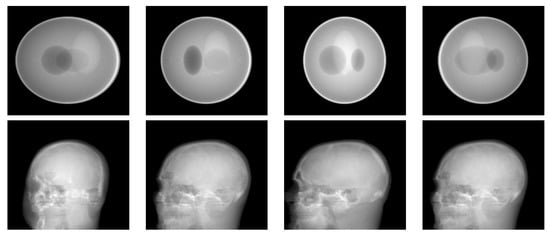

3.2. Simulation Results with a Limited Number of Projections

3.3. Simulation Results with a Limited Angle of Projections